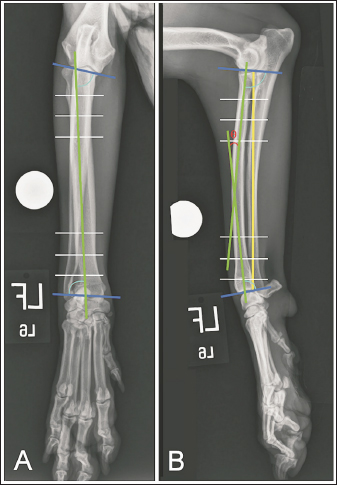

Fig. 1. Orthogonal radiographic images illustrating how joint reference lines (dark blue) and anatomic axes (green) were established to define the proximal and distal anatomic radial joint angles (light blue) on intact limbs. White lines are paired with 10% (outermost lines), 20% (middle lines), and 30% (innermost lines) markers along the length of the proximal and distal radius used to define anatomic axes. Radial length (yellow) was measured as the distance between the caudal margins of the articular surface of the radial head and of the distal radial articular surface. Theta (θ) was measured as the acute angle created at the intersection of anatomic axes.

Mixed breed dogs euthanized for reasons unassociated with the study were obtained. All cadavers had been previously frozen but were thawed and stored in a cooler for a minimum of 3 days prior to use. Bilateral orthogonal radiographs were obtained (Vet-ray, Sedecal, Niles, IL) of the antebrachium and manus to ensure normalcy and allow for preemptive measurements of antebrachial morphology. A 25-mm diameter sphere was placed adjacent to the radius in all images to allow for image calibration. Image analysis was performed on a dedicated computer using DICOM viewing software (MergePACS, Merative, Ann Arbor, MI). Angle measurements were made using a Chrome browser protractor extension (“Protractor”, Ben Burlingham) and lengths were calculated in an orthopedic planning program (vPOP PRO, VETSOS Education Ltd., Ojai, CA). Joint reference lines, anatomic axes, radial joint angles, and frontal and sagittal plane alignments were established as described by Fox and Tomlinson (2018). Procurvatum was quantified as the acute angle (theta) created from the intersection of the proximal and distal radial sagittal anatomic axes. The radial length was measured on sagittal view images and defined as the distance between the caudal margins of the radial head and of the distal radial articular surface (Fig. 1).